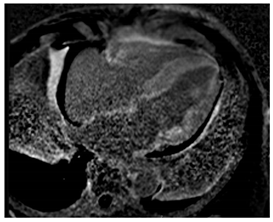

CMR is a sensitive diagnostic tool for CS, with studies yielding sensitivities between 75 and 100% []. SSFP cine imaging is used to assess for regional wall thinning or thickening, aneurysmal or dyskinetic segments, and biventricular systolic function []. In CS, native T1 mapping may be focally increased in regions of fibrosis or edema []. Native T2 mapping may also be focally increased in regions of edema if there is active inflammation []. Black-blood T2 weighted imaging can improve the detection of myocardial edema and was found to have comparable diagnostic performance to FDG-PET in a retrospective study [].

The hallmark of CMR in CS is the evaluation of LGE. LGE can reflect edema in the acute inflammatory phase and replacement fibrosis in the chronic stage of CS. LGE is often patchy, mid-myocardial and/or subepicardial, and involves the basal LV segments and RV portion of the septum [,]. Sometimes, the LGE may be transmural or subendocardial, mimicking an ischemic pattern []. FDG-PET imaging complements CMR, and combining both modalities has been shown to enhance the certainty of CS diagnosis []. In a meta-analysis of histologically proven cardiac sarcoidosis, Okasha et al. found that the lack of any myocardial LGE or the presence of isolated midmyocardial, subendocardial, or transmural LGE were rarely to never present []. This highlights the potential role of certain LGE patterns on CMR in excluding cardiac involvement in sarcoidosis. Key CMR findings in CS are summarized in Table 4.